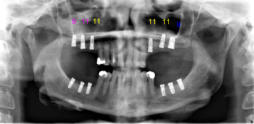

Beispiele für komplexe implantologische Versorgungen aus unserer Gemeinschaftspraxis

(Planung / Endversorgung -- als Röntgenaufnahmen)